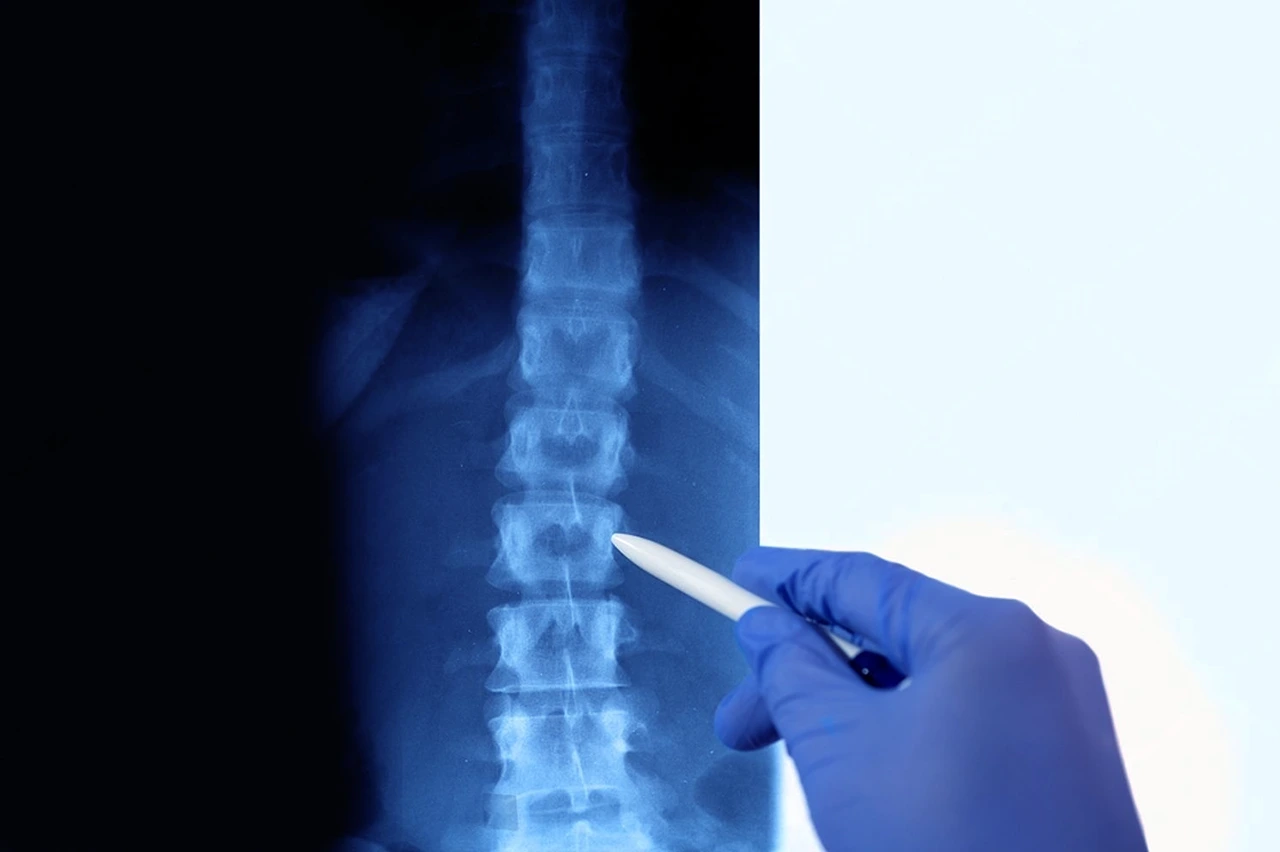

Esta evaluación se realiza a través de la observación en los planos frontal, sagital y transversal; adicionalmente es posible utilizar herramientas como plataformas de presión, escáneres tridimensionales, fotografías para análisis postural o radiografías.

Médico analizando la presencia de alteraciones posturales en un paciente a través de una radiografía, y señalando con un bolígrafo el área afectada.

Para el diagnóstico de una alteración postural se parte de un análisis detallado del cuerpo en bipedestación, esto quiere decir erguido en las extremidades inferiores; en sedestación que es al estar sentado; y en movimiento. Aquí se pueden observar signos como inclinación de hombros, rotación de pelvis, curvaturas excesivas en la columna como la hiperlordosis, hipercifosis y escoliosis; así como que haya distribución desigual del peso.